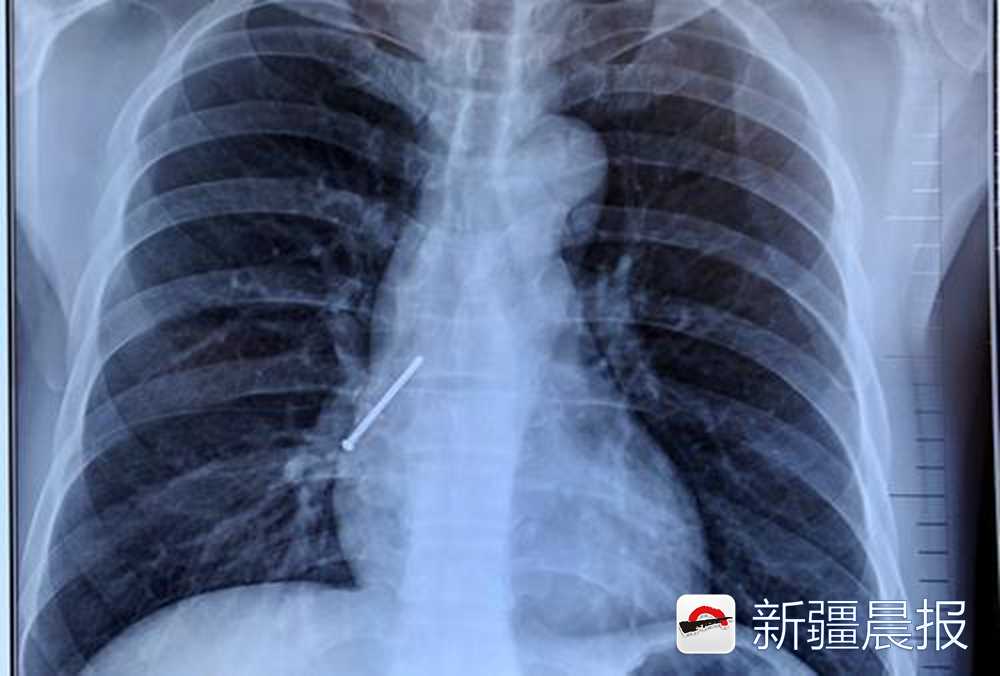

透视胶片显示:一枚铆钉停留在患者的肺部。

援疆专家、该院呼吸科副主任高金柱说:“患者来院时有咳嗽、胸闷,痰中带血的症状,经胸片影像显示,金属异物并不在胃里,而是卡在患者右肺中间段的支气管处,如果不及时取出,随着患者的呼吸,异物继续向下滑动,容易造成患者咯血窒息死亡,我们决定立即实施经气管镜异物取出术。”

经测量,这枚金属的铆钉长4厘米。